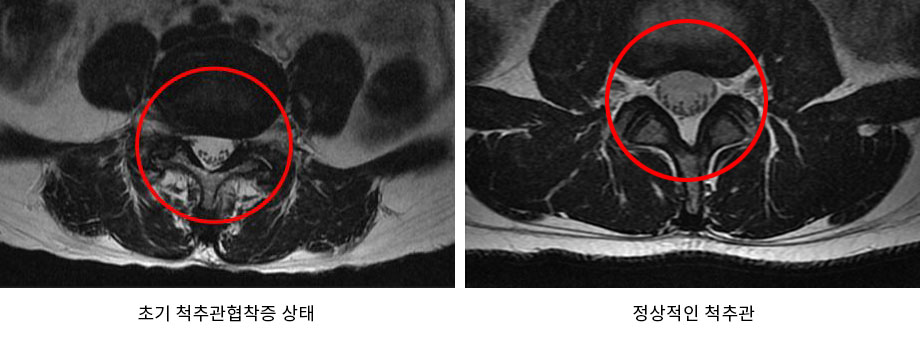

우리 몸의 중심을 잡고 체중의 대부분을 지탱해주는 척추는 나이가 들수록 퇴행되어 기능이 약해지게 됩니다. 이에 대표적인 척추질환이 퇴행성 척추관협착증입니다. 척추관협착증은 척추를 둘러싸고 있는 근육과 인대가 퇴행 되어 제 기능을 하지 못하게 되면서 척추관 내 인대가 비정상적으로 부풀어 올라 척추관의 공간이 줄어들게 되어 통증이 발생하는 질환입니다. 이러한 퇴행성 척추관협착증은 50, 60대 이상에서 발병률이 높은 질환으로 이를 방치할 경우 통증이 극심하여 거의 걷지 못하게 될 수도 있으므로 의심되는 증상이 나타난다면 초기에 치료시기를 놓치지 않는 것이 좋습니다.

일반적으로 척추관협착증 초기에 치료를 시작한다면, 특히 퇴행이 극심하지 않은 초기에 치료를 시작할 경우 아침에 일어났을 때 뻣뻣했던 증상이나 오후가 되면 뻐근했던 다리 통증은 거의 없는 단계까지 회복이 될 가능성이 있습니다. 그러나 초기 협착증일 때 적절한 치료를 시작하지 않고 방치하게 되면 시간이 지날수록 중증 척추관협착증으로 진행될 가능성이 높아집니다. 중증 척추관협착증으로 진행이 되면 실제 걸을 때 통증이 발생하며 걷는 거리가 점점 짧아지게 됩니다. 또한 중증 척추관협착증은 치료 자체는 잘 된다고 하더라도 치료의 결과는 초기와 비교했을 때 다소 떨어질 수밖에 없습니다. 즉, 척추관협착증은 척추의 퇴행 정도와 증상의 정도에 따라 치료의 결과가 달라지므로 초기일 때 치료를 서둘러 시작하는 것이 매우 중요합니다. 간혹, 증상은 심하지 않으나 퇴행이 극심한 경우가 있습니다. 이런 경우 한번 증상이 발생하게 되면 급속도로 악화될 수 있기 때문에 MRI 검사와 임상증상을 꼼꼼하게 비교해봐야 합니다. 이는 증상만 초기라고 말할 수 있을 뿐 실제 척추관협착증 초기라고 보기는 어렵습니다. 이런 경우 증상이 심하지 않을 때 치료를 시작하면 증상이 악화된 후 치료를 시작했을 때보다 치료효과가 좋습니다.